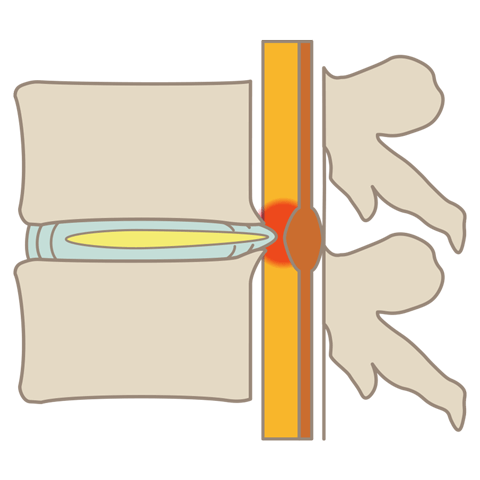

腰部脊柱管狭窄症

腰部脊柱管狭窄症とは、背骨にある神経の通り道「脊柱管」が狭くなる疾患です。腰痛や足の神経障害、歩行困難などの症状を引き起こします。